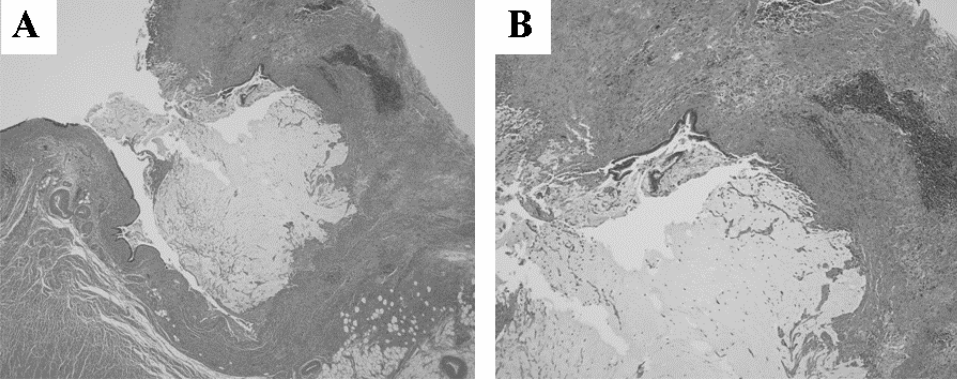

The wall of the cystic lesion was lined with intestinal epithelium without atypia associated with chronic inflammation of the appendiceal mucosa and there was mucin secreting epithelium lining the appendix (Figure 4). The lesion demonstrated the pathological features of mucinous cystoadenoma of the appendix.

Figure 4: Histopathological findings. (A) Lower magnification, (B) Higher magnification. The wall of the cystic lesion was lined with intestinal epithelium without atypia associated with chronic appendicitis obliterans and mucin secreting epithelium lining the appendix was shown.